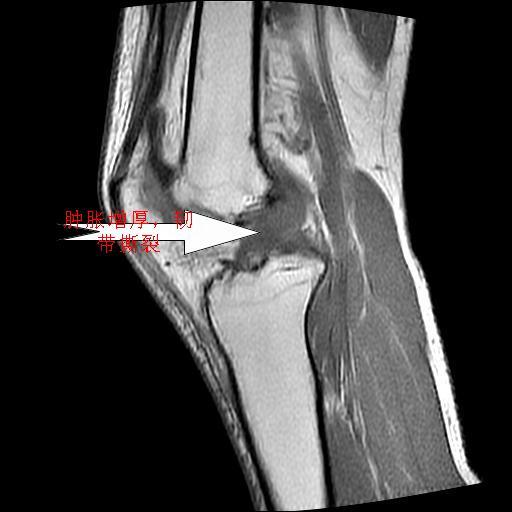

1、内侧副韧带撕裂;

2、前交叉韧带撕裂;

3、滑膜炎伴关节腔积液。

内侧副韧带撕裂及关节腔积液是肯定的,但是前交叉撕裂确定吗?会不会有容积效应的因素,因为前一张前交叉显示清楚,连续性良好,且较光滑。请问楼主有关节镜支持吗?我们医院也经常有这样的患者,但苦于没有关节镜,而无法对照、证实(除非完全断裂),出现了不同的诊断结果只能毫无意义的争论。

1、前交叉韧、内侧副韧带撕裂;

2、外侧半月板后角撕裂;

3、关节腔积液。4、髁间脊撕脱骨折。

、内侧副韧带撕裂;

2、前交叉韧带撕裂